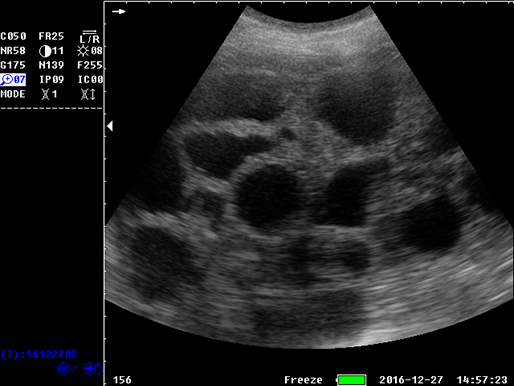

有关病变的更多见解

有关病变的更多见解